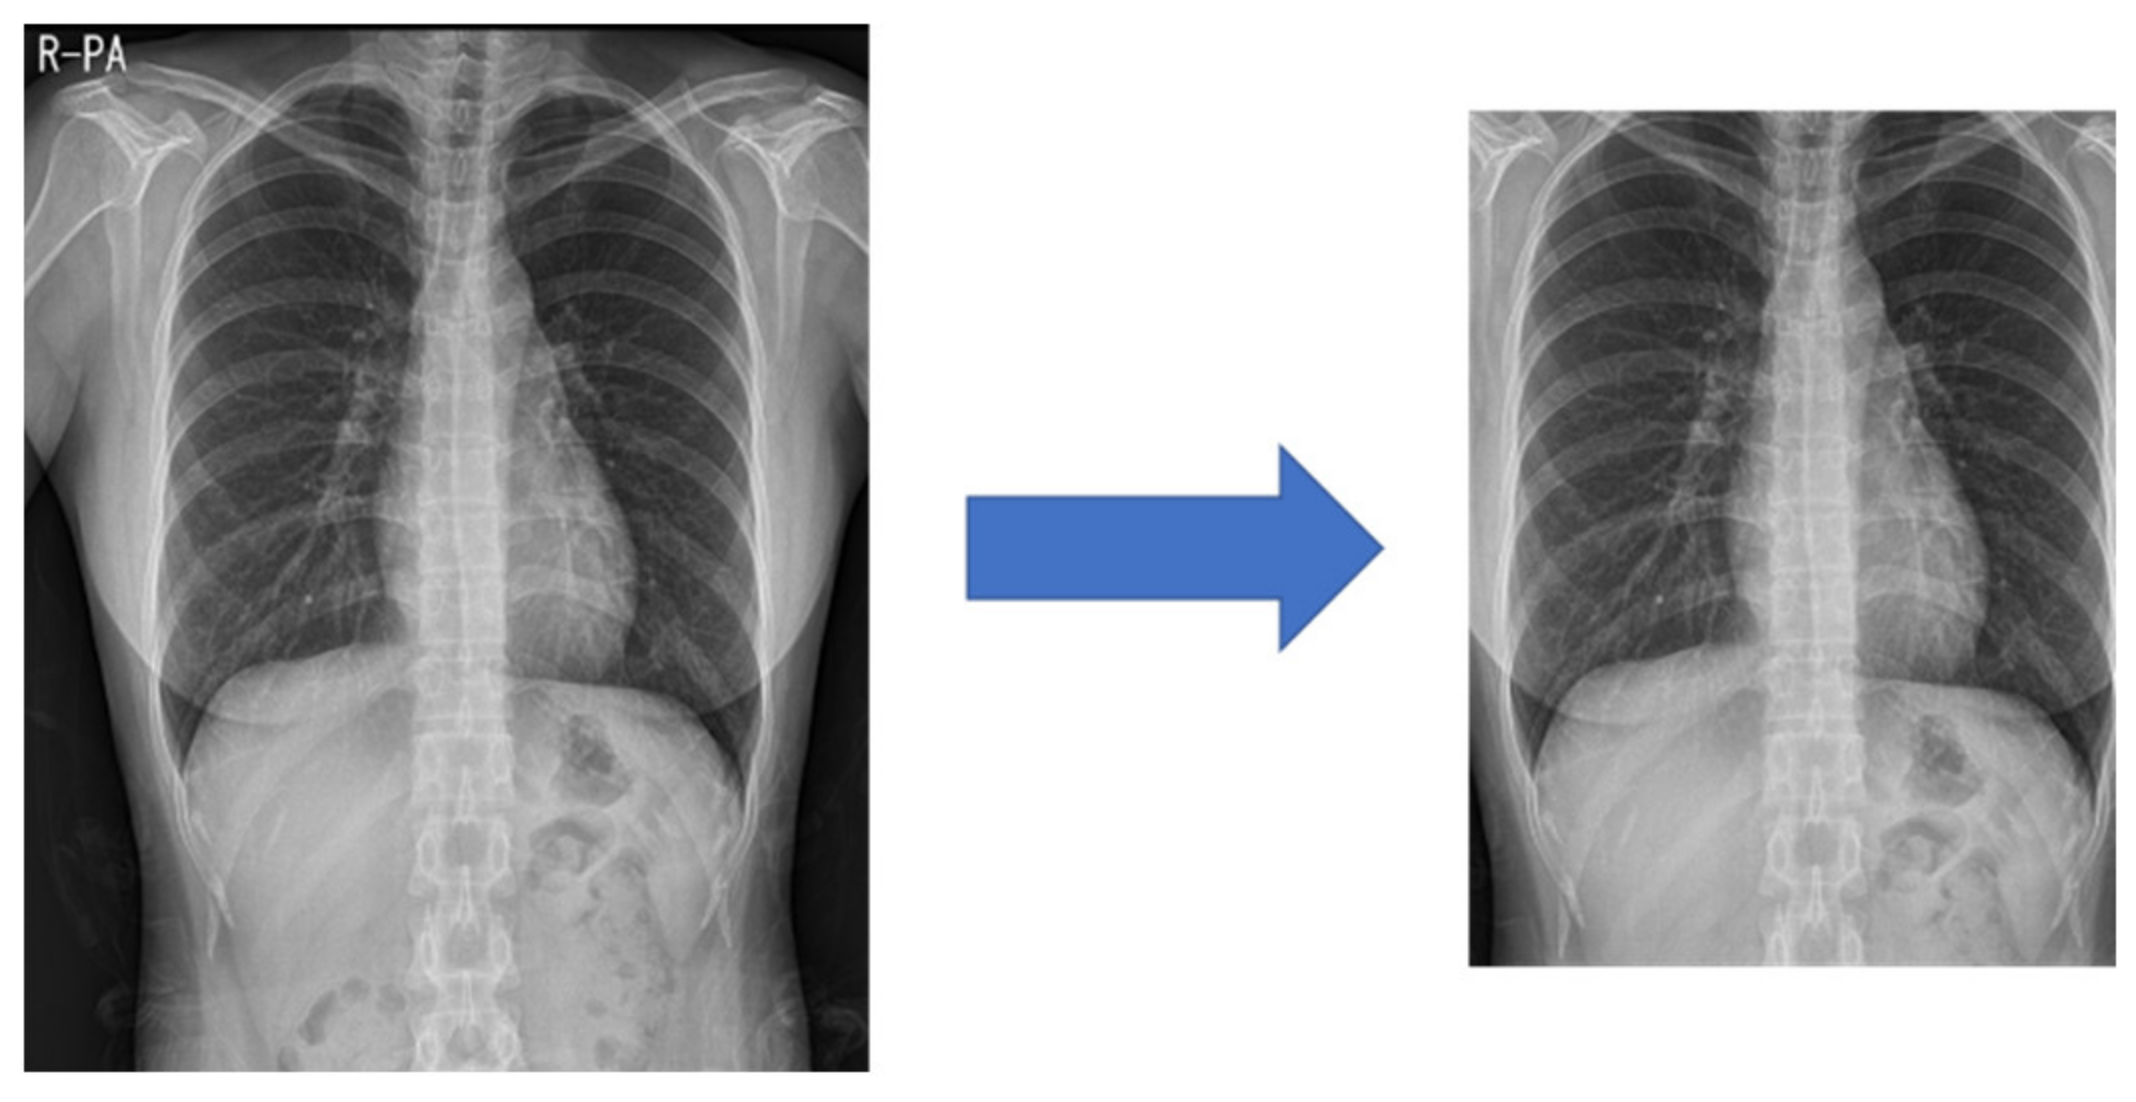

Medical images often have different heights and widths. Most deep learning research ignores this and resizes it, but in this case, the original aspect ratio of the image may be different. Therefore, in this study, to improve the learning performance, the height and width are compared, and the difference in length is cut out from the height or width. After creating a 1:1 ratio, the center pixel is cut out to a size of 87.5%, as shown in Figure 3. This preprocessed image reduces the search range of the CNN to make it easier to learn.

Figure 3. Center cropped image after processing in a 1:1 ratio.